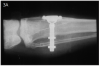

Figure 27A – Radiograph of fractured posterior implant

Figure 47A

Figure 27B – Gingiva incised and a trephine drill used to remove fractured implant

Figure 27B